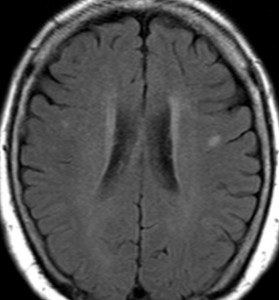

肺小細胞癌の転移 multiple metastases of lung small cell cancer

左のMRIは,肺小細胞癌の患者さんに脳転移が無いか確かめるために撮影されたものです。転移はありませんでした。右側のMRIは,そのわずか3週間後に撮影したものです。数十個の脳転移がありました。肺小細胞癌では短期間の間に無数の脳転移を生じることがあります。かつては脳転移を予防するための予防的全脳照射という治療が行われていたくらいです。